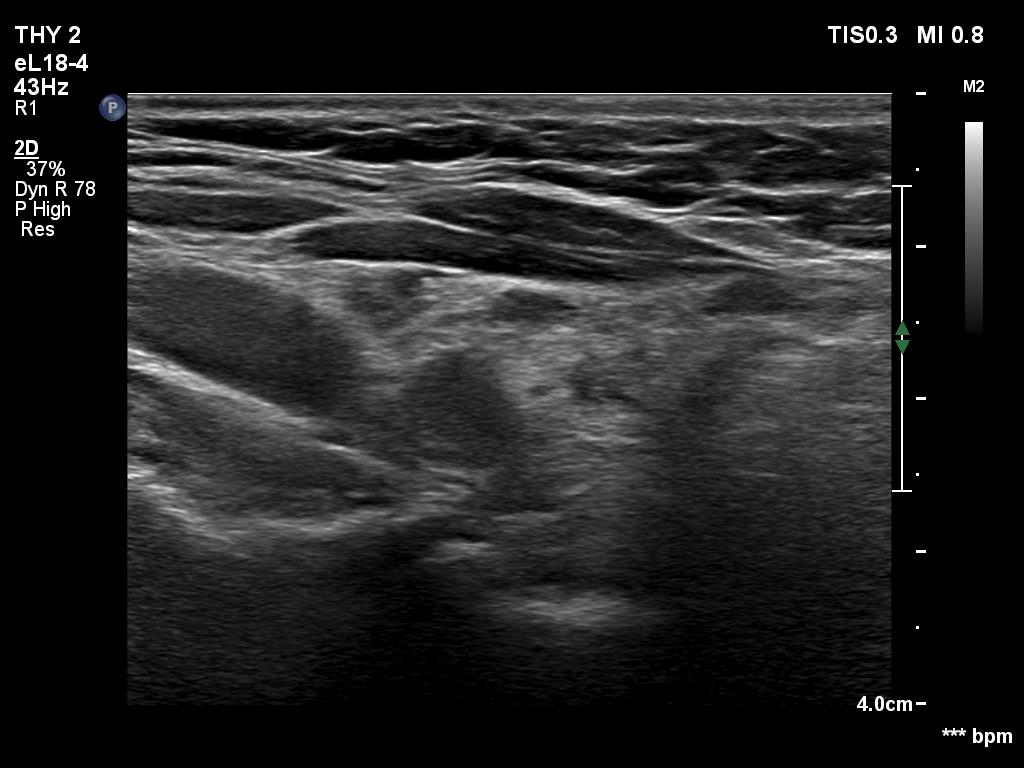

A patient operated on Graves' disease then received radioiodine therapy - case 321

After the surgery before the radioiodine treatment

After the radioiodine treatment

The patient had a recurrent hyperthyroidism 15 years after a bilateral subtotal resection performed because of relapsing Graves disease. Several months after the first visit, the patient underwent on radioiodine treatment. The right images were recorded 5 years after the isotope therapy.

In surgically treated thyroids, the histopathological findings must be taken ito account in order to avoid mispretating discrete lesions. If the previous histopathology did not find nodule than an ambiguous lesion is very rarely a true nodule.

The echonormal areas which surround the hypoechoic lesion can be tracked up, down and sideways, therefore these do not correspond to thyroid tissue but to connective tissue.